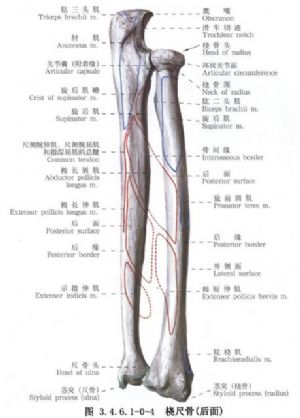

尺桡骨干骨折常见。由于暴力的原因和受伤瞬间肢体的姿式以及肌肉收缩的状态不同,可以发生尺桡骨干双骨折或单骨折。其中,又可发生于不同平面。尺骨干上1/3骨折合并桡骨小头脱位(孟氏骨折Montaggia fracture)。桡骨干下1/3骨折合并下尺桡关节脱位(盖氏骨折Galeazzi fracture)。其中尺桡骨干双骨折占全身骨折的5.41%,为第3位。桡骨骨折占4.23%,为第5位。尺骨骨折占1.05%,为第17位。孟氏骨折占0.63%,为第38位。盖氏骨折占0.35%,为第50位。由于前臂具有旋转功能,一旦发生骨折,除重叠和侧方移位外,尚有严重的旋转移位。因此,对复位的要求较高。如手法复位不满意,难以达到预期功能的恢复,即有手术复位的指征。相关解剖及影像表现见下图(图3.4.6.1-0-1~3.4.6.1-0-6)。